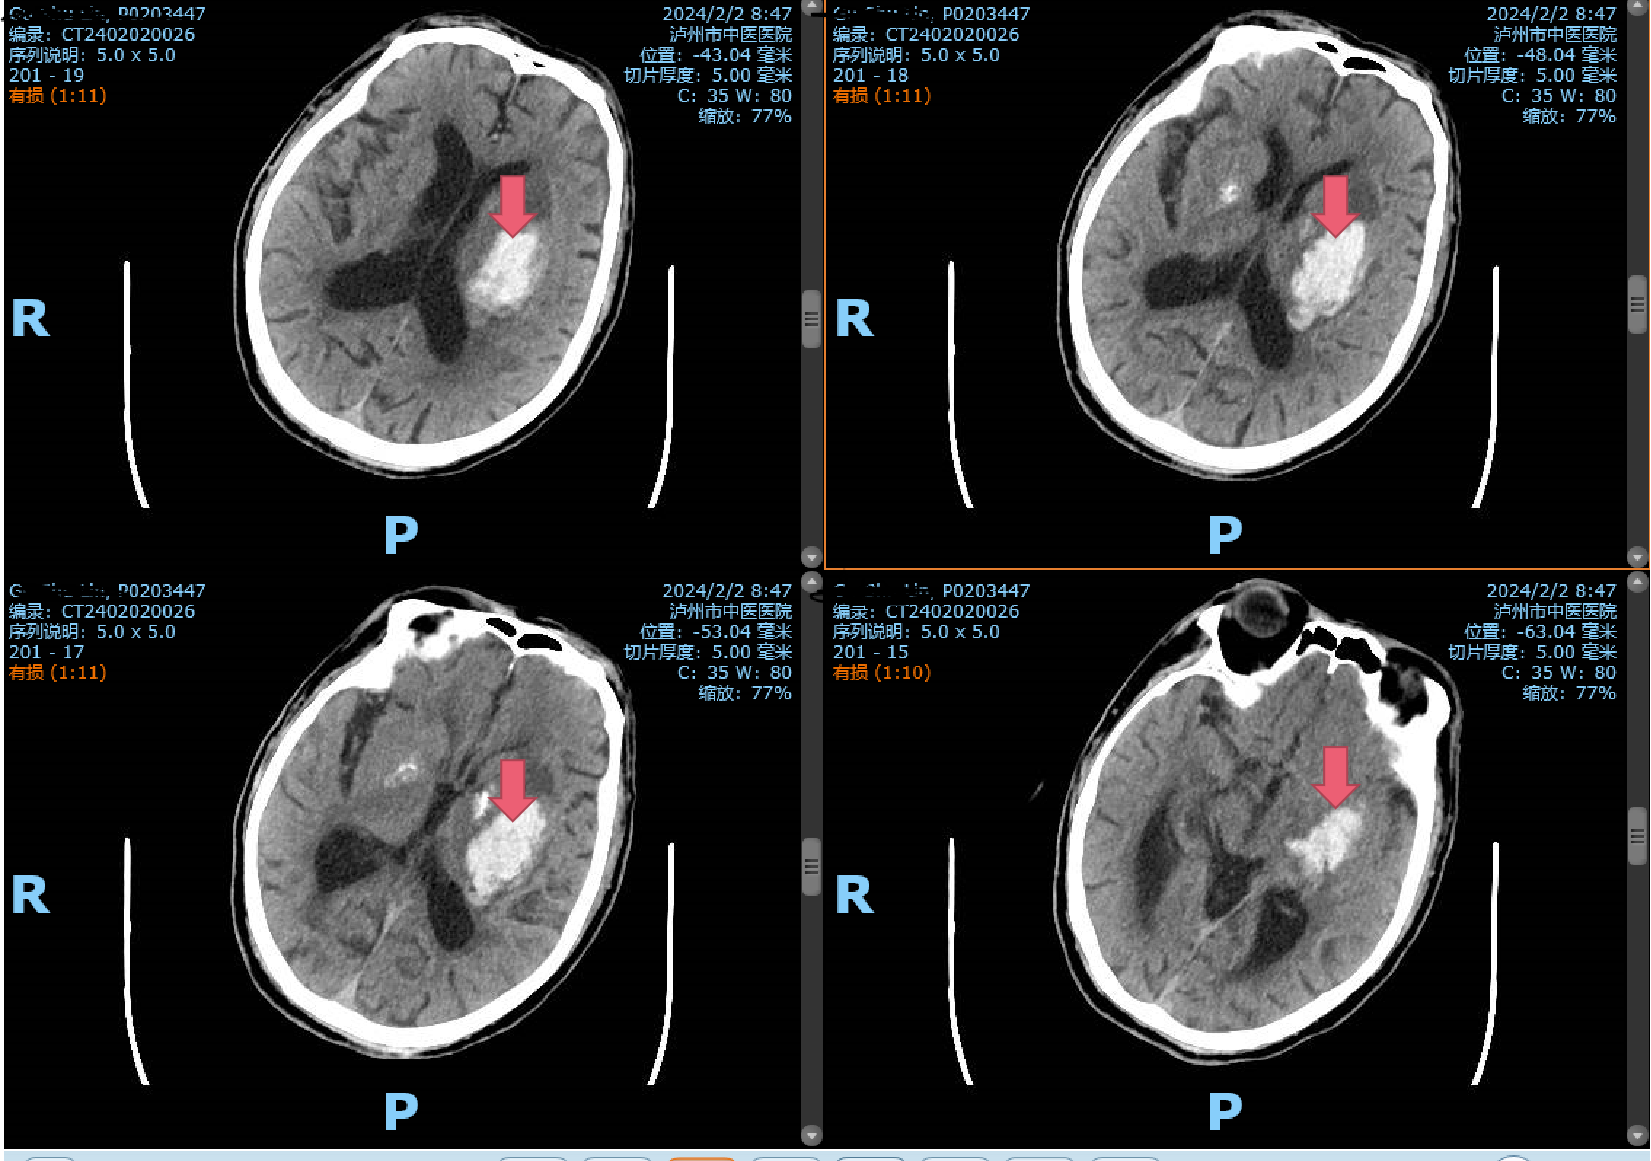

2月2日一早,一陣急促的響鈴聲打破了清晨的寧靜,一位年逾古稀的辜先生在洗澡時突發(fā)一側(cè)肢體無力,家屬見狀不知所措,焦急萬分,情急之下將患者背下樓,直接送入瀘州市中醫(yī)醫(yī)院急診科!時間第一,生命至上?;颊呷朐汉笾苯咏?jīng)急救通道,完善頭顱CT,提示腦出血,病情危重,立即及時、安全地送到了市中醫(yī)院重癥監(jiān)護室,并...